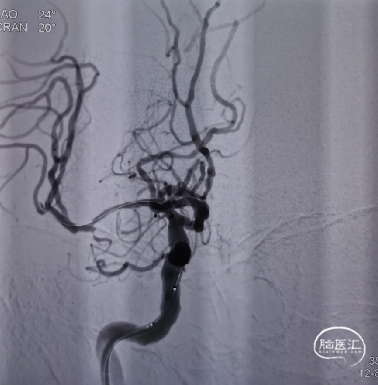

经微导丝送入XT-27微导管至大脑中动脉上干M2段;经微导管释放颅内支架(2.5mm*20mm Neuroform EZ),完全覆盖狭窄段;再次造影见支架定位良好,前向血流通畅,充分覆盖狭窄段及夹层病变。

3D旋转造影及颈总动脉正侧位造影显示支架张开良好,大脑中动脉远端分支存在。